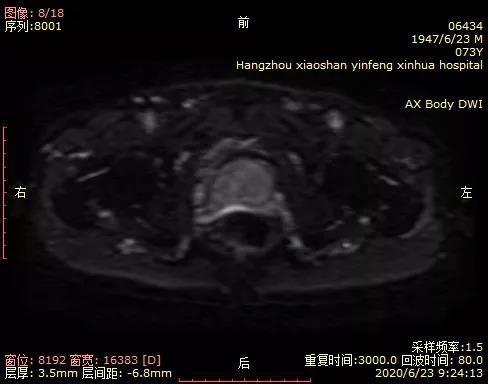

05 磁共振新技术的应用 前列腺弥散加权成像(DWI)对前列腺癌定性诊断有重要意义;可以作为PSA值异常后的常规筛查。